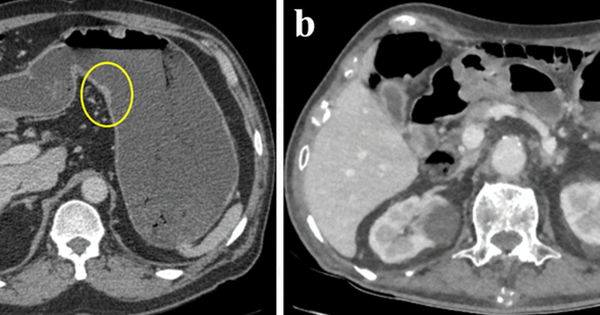

Bác sĩ Lê Huy Lưu, phụ trách điều hành Khoa Ngoại Tiêu hoá, Bệnh viện Nguyễn Tri Phương đánh giá mặc dù đường kính khá to nhưng độ ăn sâu vào thành dạ dày chưa nhiều. Các bác sĩ của Khoa Nội soi, Ngoại tiêu hoá, Chẩn đoán hình ảnh đã hội chẩn và sử dụng phương pháp cắt lớp điện toán để đánh giá chính xác vị trí khối u. Quy trình đặc biệt được sử dụng là chụp với dạ dày được làm căng bằng nước.

Bên trái: dạ dày được làm căng, khối u nhỏ được phát hiện (trong vòng tròn). Bên phải: dạ dày chưa được làm căng (Ảnh: BVCC)

Với quy trình đặc biệt này, bác sĩ Lưu cho biết thành dạ dày sẽ được làm căng ra, xoá mất các nếp gấp của niêm mạc dạ dày giúp khối u dạ dày dễ dàng được phát hiện và hạn chế nhầm lẫn; cho biết chính xác vị trí của khối u cũng như xác định được khoảng cách từ khối u tới chỗ nối dạ dày với thực quản.